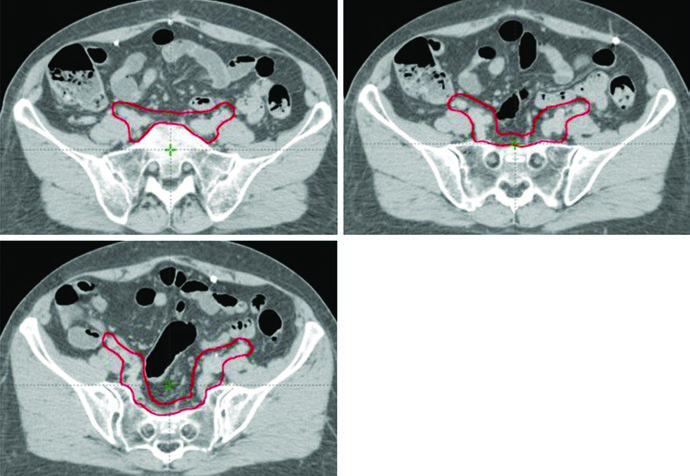

Extended Fields and SIB Boost

Extended field radiation therapy is often indicated when pathologic involvement of para-aortic or high common iliac nodes is confirmed. In these cases, the upper border of CTV3 may extend to the T12-L1 or L1-L2 interspace, or to the renal vasculature. Modified extended fields with upper borders between L4-L5 and L1-L2 may be used in patients with extensive pelvic nodal or high common iliac nodal involvement.

A boost of 5-15 Gy may be added for gross nodal disease or parametrial involvement, delivered either sequentially or as a simultaneous integrated boost (SIB). The textbook illustrates a patient with FIGO stage IB endometrioid adenocarcinoma, post robotic-assisted laparoscopic hysterectomy, who had an enlarged para-aortic lymph node found at CT simulation. She was treated with extended field IMRT using an ITV technique. The superior border of CTV3 was modified to include the renal hilum, the GTV of gross nodal disease was contoured, and it received a planned SIB boost of 5940 cGy with 4760 cGy in 28 fractions to the remaining nodes.

The SIB approach allows treating gross nodal volumes with escalated dose without adding extra fractions. In clinical practice, the choice between SIB and sequential boost depends on case geometry and dose constraints to adjacent organs at risk. For complementary approaches in definitive gynecologic IMRT, see the dedicated article.